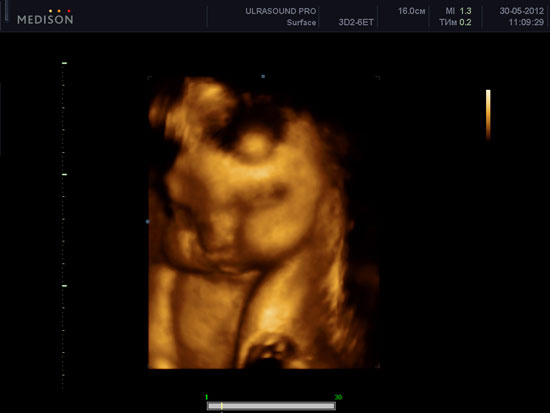

Ваша дитина при УЗД плоду в 32 тижні вагітності.

При УЗД плоду в 32 тижні вагітності, особливо із застосуванням 3D-4D УЗД при вагітності , Можна побачити очі дитини. Майже завжди вони закриті, так як у водному середовищі плоду не дуже приємно тримати очі відкритими. Але це зовсім не означає, що ваш малюк постійно спить! Колір очей у всіх дітей з даного терміну вагітності до моменту пологів темно-сірий. Істинний колір проявляється через деякий час? від 3 тижнів до 12 місяців, це індивідуально.

При УЗД плоду в 32 тижні вагітності можна побачити, як дитина продовжує тренуватися для того, щоб бути готовим до поза утробного життя зовсім скоро! Він ковтає навколоплідні води, проводить дихальну гімнастику для легких (дихальні руху), смокче пальчик, штовхається ніжками і ручками.